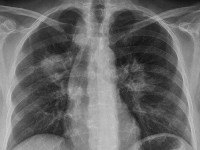

Ulcera bij ziekte van Wegener Longafwijkingen bij ziekte van Wegener PA ziekte van Wegener

X-thorax: Tom Buur - Wikimedia (Creative Commons License 3.0).

Labdiagnostiek: X-thorax (noduli, infiltraten, granulomen), urinesediment (microhematurie), biopt (granulomateuze infiltraten in of rond bloedvaten), ANCA's (m.n. anti-PR3 ANCA (c-ANCA) is zeer suggestief voor Wegener). De ANCA's bij Wegener zijn vooral van het c-ANCA type, gericht tegen een 29 kD-serine protease uit azurofiele granula van myeloïde cellen, ook wel proteïnase-3, PR-3 of 29kD eiwit genoemd).

2. Abnormal chest radiograph

Chest radiograph showing the presence of nodules, fixed infiltrates, or cavities